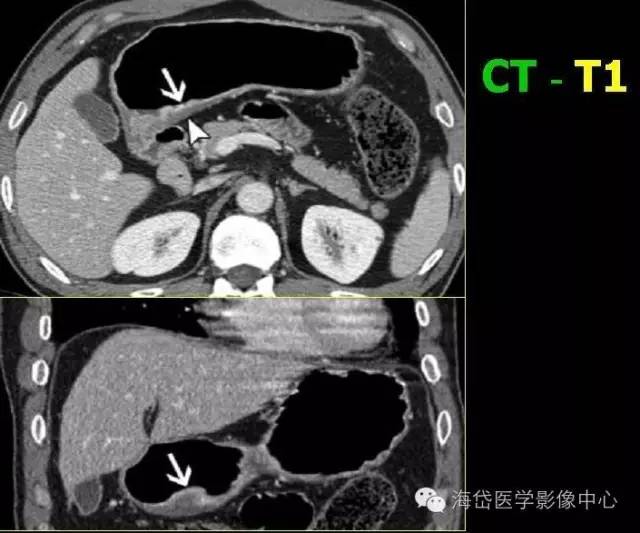

T1:低密度的粘膜層保持完整

T2:胃壁增厚,低密度帶中斷,外輪廓光滑,周圍脂肪層清晰條索影少于1/3